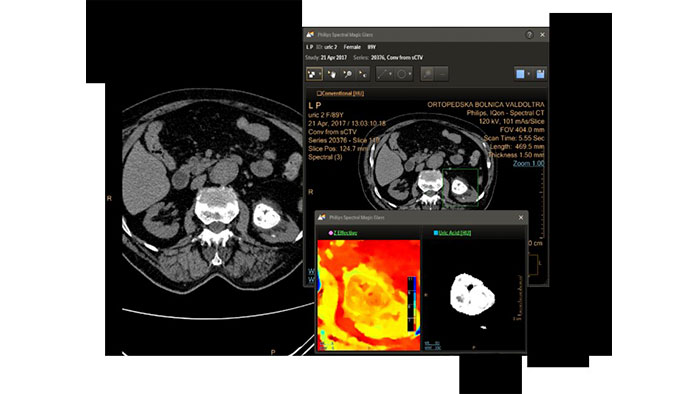

Spectral Advanced Vessel Analysis

CT Spectral Advanced Vessel Analysis

IQon Spectral CT Functionality

Benefits

• Bone removal on different energy levels.

• Spectral plots to characterize plaque and stenosis.

• Different energy results comparison.

• Evaluation of the extent of lumen occlusion.

Spectral Comprehensive Cardiac Analysis

CT Spectral Comprehensive Cardiac Analysis

Provides the ability to run cardiac segmentation on different energy levels, compare vessel curves with various spectral data types, and enhance the visual assessment of coronary vessel patency.

• Automatic chamber and coronary segmentation using mono-energetic images.

• Beam hardening reduction for: perfusion deficits visualization and calcified plaque visualization.